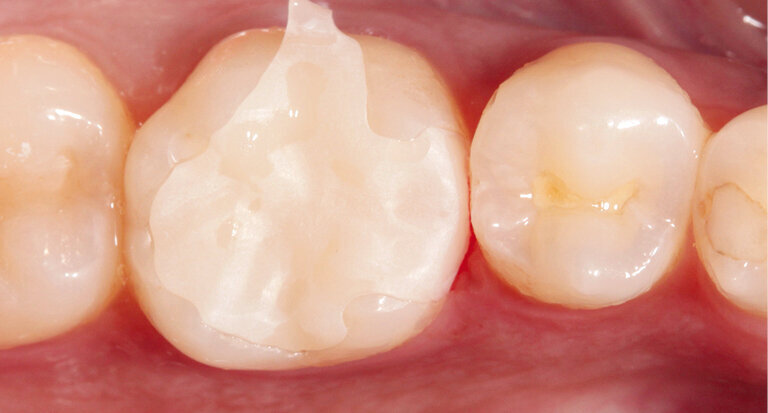

In the present case, a try-in was performed immediately after the grinding process to check the fit of the inlay with the natural residual tooth structure (Fig. 4).